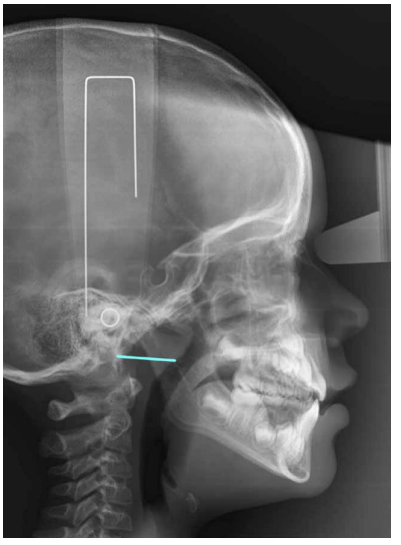

Finalmente se midió la distancia que se extiende el punto de intersección de la pared faríngea posterior y la línea que se forma entre la espina nasal posterior junto con basion (Ad1-Ba) (Figura 3).